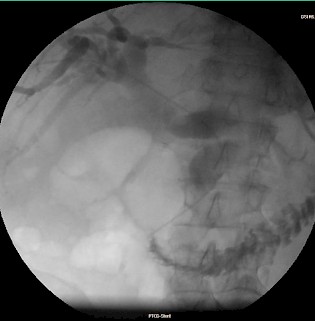

Im Falle einer Stenose oder eines kompletten Verschlusses eines Gallenganges ist es möglich, über diesen Punktionsweg eine Ableitung der Gallenflüssigkeit nach außen durch die Haut über eine Drainage (Plastikschlauch mit mehreren seitlichen Löchern) herzustellen (perkutane transhepatische Cholangiographie und Drainage, PTCD). Die Gallenflüssigkeit sammelt sich dann in einem kleinen Plastikbeutel. Hierdurch kann die Gallenflüssigkeit abfließen und der Aufstau der Gallenwege geht zurück. Eine solche externe Drainage beeinträchtigt die Lebensqualität (Drainage muss alle 4-6 Wochen gewechselt werden; Duschen oder Schwimmen mit der nach außen abgeleiteten Drainage nur schwierig möglich). Daher versucht man, wenn möglich, die Einlage einer metallischen Gallengangsprothese (Stent). Die Stents können je nach der zugrundeliegenden Grunderkrankung über viele Monate auch ohne eine Außenableitung den internen Gallenabfluss ermöglichen.

Fallbeispiel:

Patient mit Pankreaskopf-Ca, Leber- und Lungenmetastasen und Tumorverschluß des Gallengangs: